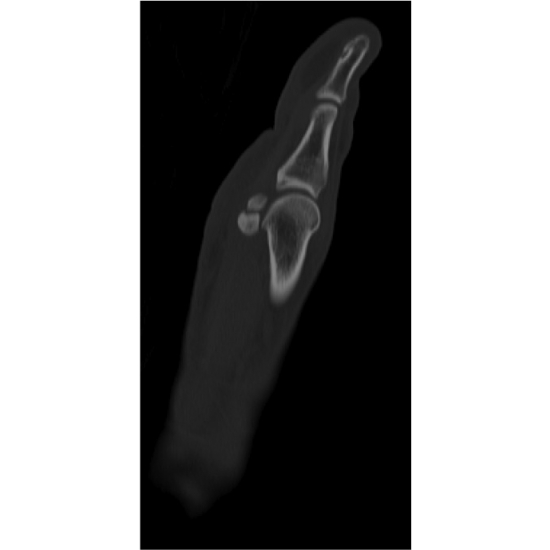

| Open Sesamoid: Medial Forefoot Pain In A Soccer Player - Page #3 | |||